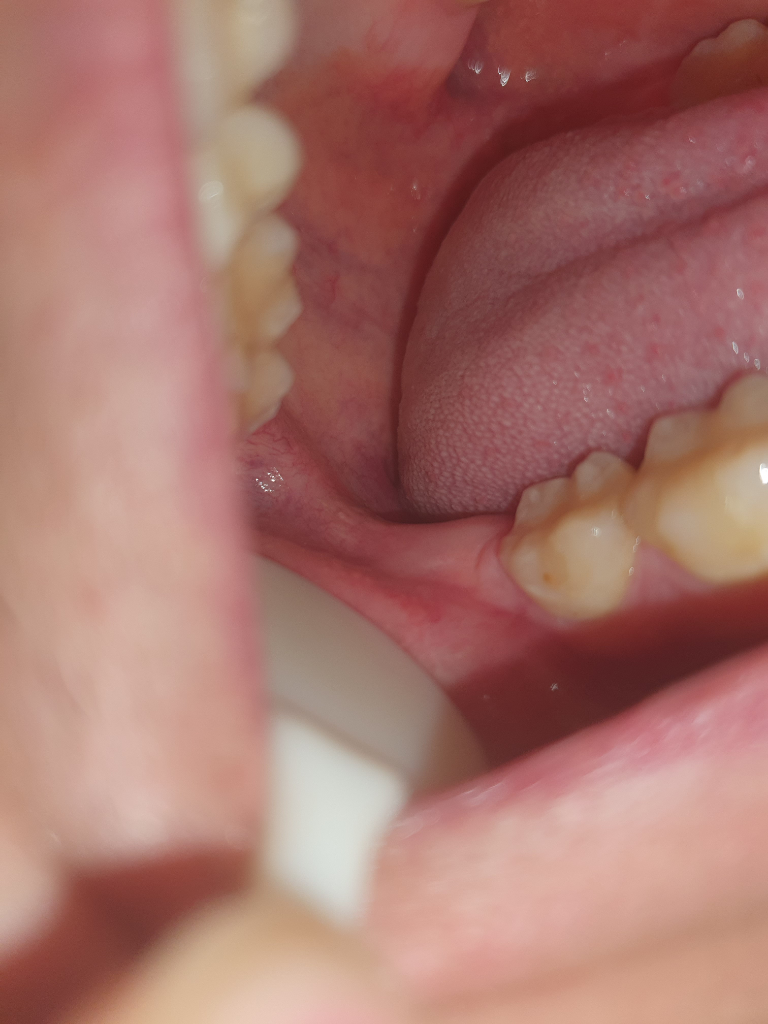

• 2번 째 사진

치과 방문이 필요합니다. 어금니 뒤쪽에 농양이 있을 가능성이 매우 높습니다. 사랑니 발치로 인하여 나타난 농양이라고 무조건 할 수는 없으며 앞쪽 어금니에 의해서 나타날 수도 있어 보입니다. 잇몸이 부어 있고 해당 부위에 농이 있을 가능성이 크므로 이를 제거하는 것이 맞아 보입니다. 치과를 빨리 방문하시길 바랍니다.

사진상으로는 크게 문제가 없어 보입니다. 사랑니 발치한곳보다는 그 앞쪽치아 뒷편에 염증이 생겻을 가능성이 잇으니 치과에 가셔서 그쪽잇몸치료를 한번 받아보세요.

사진으로 봤을 경우에는 큰 문제가 보이지는 않습니다.

사랑니를 발치하고 내부에 생긴 공간으로 이물질이 들어가서 나오지 못하는경우에 내부에서 염증을 이일으키는 경우가 있기 때문에 이런경우에는 염증을 줄어주기 위햇 원인을 제거해야 해요.

방사선 사진을 찍어서 확인을 해봐야 할것으로 생각됩니다.